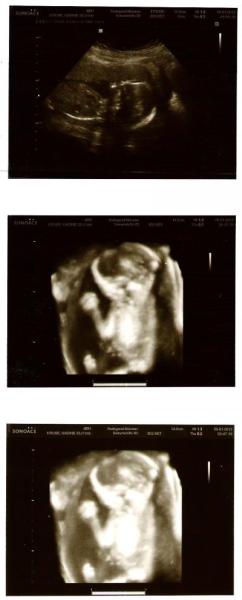

Heute war dann auch mal mein Freund mit und meine FA hat sich richtig Mühe gegeben. War auch mal eine Traumuntersuchung. Diesmal war der Urin auch mal total ok. Nix drin, was nicht auch drin sein sollte. Die Wunde nach der OP ist auch gut verheilt aber sie hat mich noch eine Woche krankgeschrieben. Hat auch heute mal nach dem Geschlecht geschaut weil mein Freund fragte... tja sie hat zumindest eine vermutung abgegeben.. hihi... Heute waren wir auch sehr aktiv und boxten ganz schön rum, jetzt kann ich auch mit gewissheit sagen: " ja ich bemerke die Kindsbewegung und es ist nicht nur mein Darm oder ähnliches :-)" Am 26. habe ich dann jetzt auch einen Termin zur Feindiagnostik bei einem Spezialisten bekommen. Hoffe es ist da dann auch alles ok. Auf jeden Fall war meine FA sehr zufrieden mit uns...freu Ach ja... heute haben wir Bergfest... jipppiiihhhh20